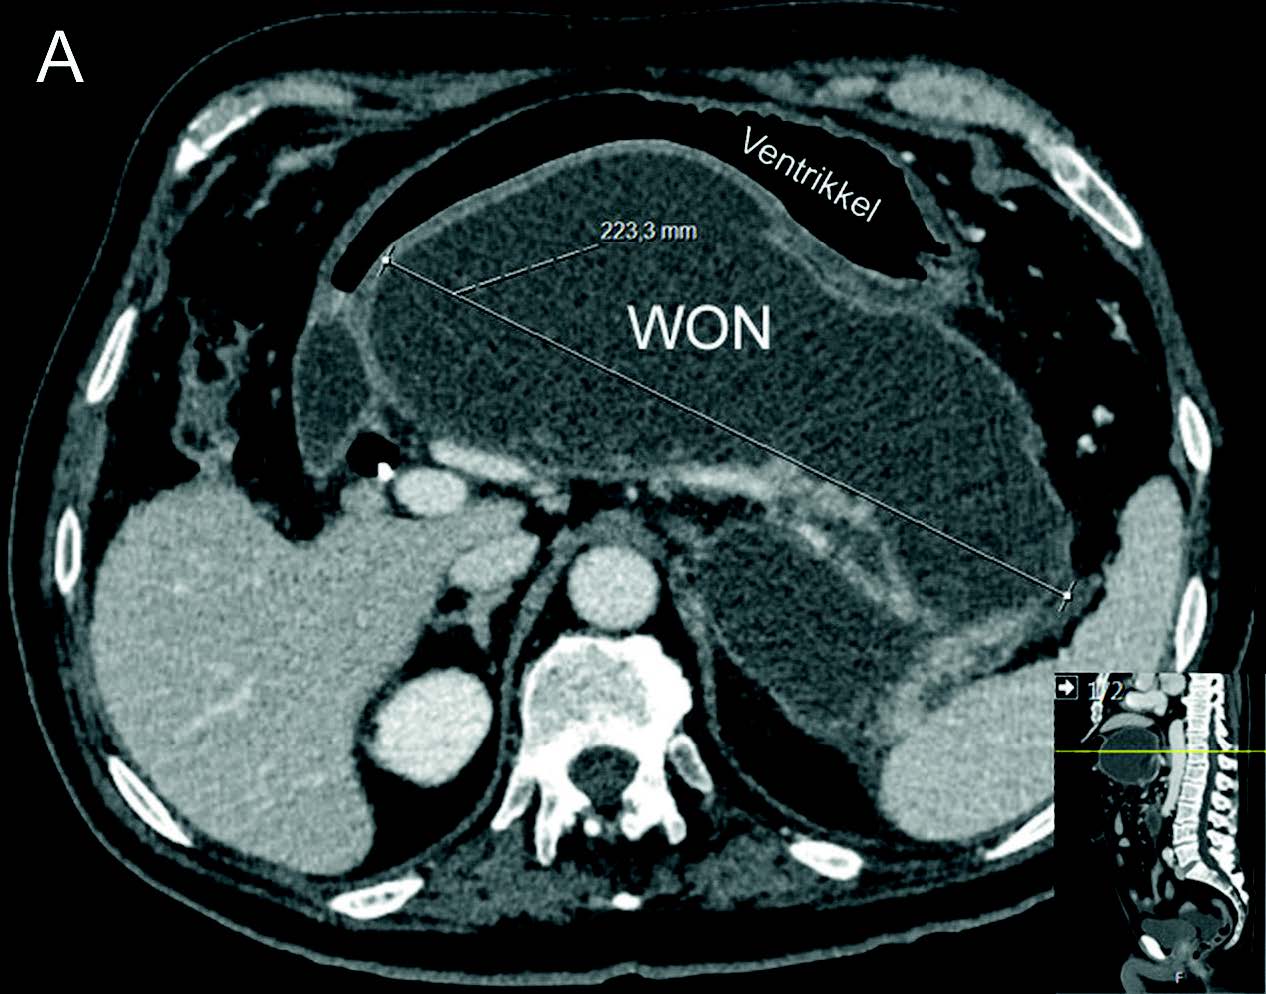

Akutt pankreatitt har et alvorlig forløp hos ca. 20 % av pasientene med utvikling av pankreatiske og/eller peripankreatiske nekroser (nekrotiserende pankreatitt) og truende multiorgan affeksjon. Disse pasientene kan ha et langtrukkent forløp med uker og måneder på sykehus. Forløpet er typisk 2-faset hvor den første uken (tidlige fase) er preget av systemisk inflammatorisk responssyndrom (SIRS) og organsvikt, etterfulgt av en sen fase (etter 1-2 uker) der komplikasjoner kan oppstå som følge av infeksjon i nekrotisk vev, kompresjon/obstruksjon av gallegang og/eller GI tractus, pseudoaneurismer, lekkasje fra pankreasgang, m.m. I den sene fase vil nekrosene gradvis innkapsles i lokulamenter kjent som WON, og hos ca. 50 % av pasienten vil disse kreve invasiv behandling. Behandlingen av WON har gjennomgått en revolusjon de senere år hvor man nå ikke intervenerer mer enn nødvendig og så sent som mulig ut fra det kliniske bildet («step-up» strategi). Endoskopisk transmural drenasje har blitt standard behandling og første valg fremfor tradisjonell kirurgisk drenasje. Indikasjoner for endoskopisk drenasje er de samme som for kirurgisk drenasje: mistenkt infiserte nekroser (vanligste indikasjon), obstruksjon/kompresjon av GI tractus/gallegang eller manglende klinisk bedring i senforløpet («failure to thrive»). Som hovedregel må man vente til nekrosene er demarkert (synlig kapsel på CT) og man har en etablert WON, det vil si minst 3-4 uker eller senere ut i forløpet. Gode CT bilder og/eller MR bilder (helst < 1 uke gamle) er viktig for å få informasjon om størrelse og utbredelse av WON, andel nekroser i kaviteten, avstand fra ventrikkel (duodenum), pseudoaneurismer og eventuelle større blodkar (f.eks. miltkarene) i relasjon til kaviteten samt tilstedeværelse av gastriske varicer, både med tanke på risiko i relasjon til prosedyren og risiko for et mer langvarig forløp hvor det bl.a. kan bli behov for nekrosektomi. Endoskopisk drenasje bør bare gjøres dersom multidisiplinært team er tilgjengelig (endoskopør, gastrokirurg, intervensjonsradiolog og anestesiolog) både med tanke på indikasjonsstilling og håndtering av eventuelle komplikasjoner i forløpet.

Samtidig med dreiningen mot primær endoskopisk behandling av infiserte nekroser har det blitt utviklet en helt ny type dekkede selvekspanderende metallstenter, såkalte «lumen apposing» metallstenter (LAMS). Stentene legges EUS veiledet og lager en kommunikasjon mellom ventrikkel (eventuelt tarm) og WON, en cystogastrostomi (Fig 1). Stentene har stor diameter (15-20 mm) og man oppnår på den måten god drenasje av nekrotisk materiale til ventrikkel. I tillegg får man tilgang til kaviteten med et gastroskop og dermed mulighet for uthenting av nekrotisk materiale (direkte endoskopisk nekrosektomi) dersom dette skulle bli nødvendig. I motsetning til eksterne kirurgiske dren er behandling med slike stenter smertefritt for pasienten.

Endoskopisk behandling er som nevnt førstelinjebehandling og bør uansett forsøkes først dersom teknisk mulig da ekstern drenasje av væskefasen og eventuell tilførsel av luft i WON kan vanskeliggjøre senere endoskopisk behandling. Tilhelingstid er normalt 4-6 uker avhengig av størrelse, utbredelse og andel faste nekroser i kaviteten, men kan hos enkelte pasienter være betydelig lenger. Stenten (LAMS) fjernes når kaviteten er borte (Fig 2).

- Fig 2: CT bilder fra pasient med nekrotiserende pankreatitt og behandlingstrengende WON før drenasje (A) og 4 uker etter (B) innleggelse av LAMS (pil).